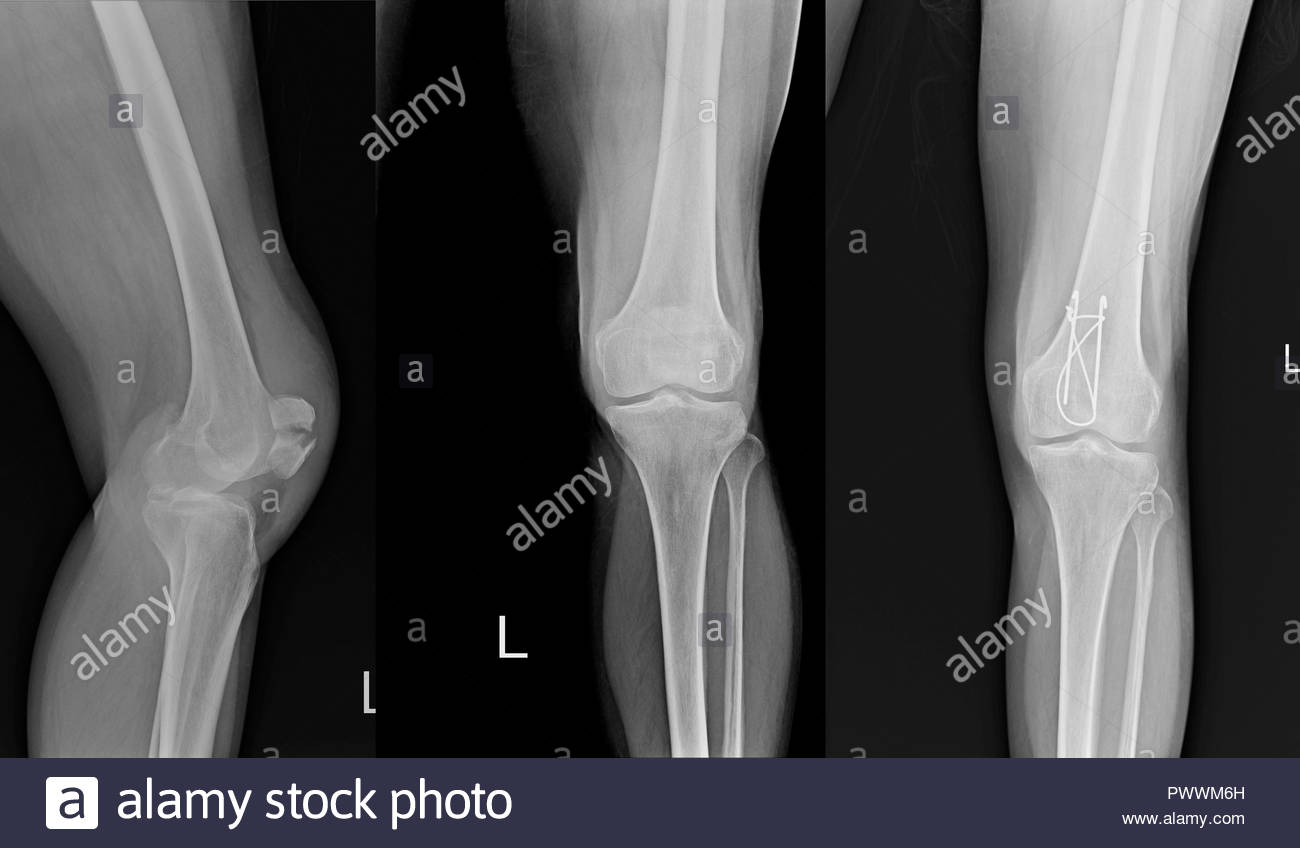

From www.alamy.com

Normal Knee X Ray Stock Photos & Normal Knee X Ray Stock Images Alamy What Should A Normal Knee X Ray Look Like There mild or borderline patella alta. Evaluating the medial proximal tibial angle. This case is a nice example of a normal exam in a 60 year old female. Normal ap and lateral knee radiographs in an adult male for reference. In order to understand problems related to our knees, we must know what is normal. Please refer to normal lower. What Should A Normal Knee X Ray Look Like.

Normal knee x ray hires stock photography and images Alamy What Should A Normal Knee X Ray Look Like Evaluating the medial proximal tibial angle. There mild or borderline patella alta. Normal ap and lateral knee radiographs in an adult male for reference. In order to understand problems related to our knees, we must know what is normal. Your technologist will take one image from the front of your knee (anteroposterior view), one. Please refer to normal lower limb. What Should A Normal Knee X Ray Look Like.